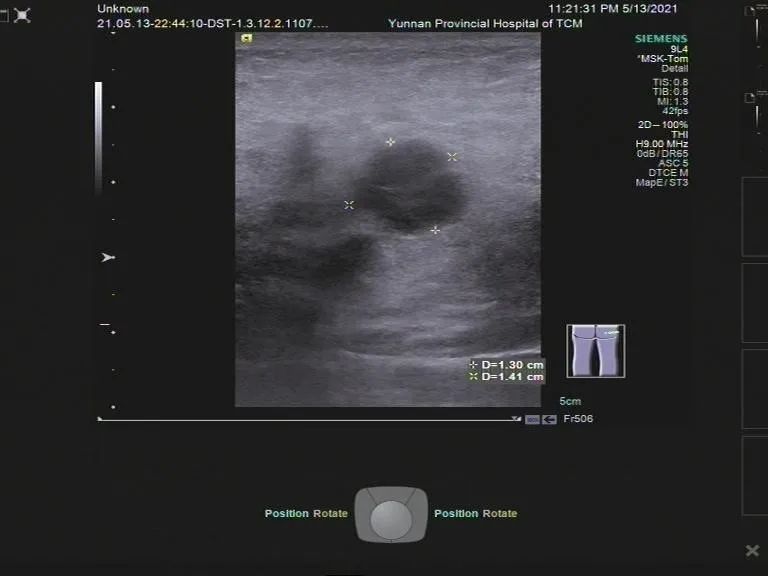

专业特长:复杂心脏血管疾病的超声诊断,肌肉骨骼超声诊断及介入性治疗